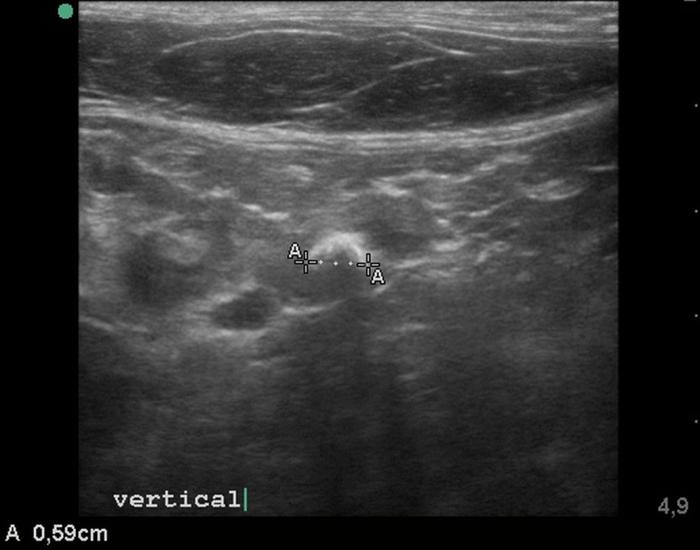

El estudio ultrasonográfico abdominal se realizó con un ecógrafo marca Mindray® modelo Z60Vet®, con transductor de 12 MHz. El estudio reveló los siguientes hallazgos (Figura 2-4):

- Hiperecogenicidad difusa e irregularidad de contornos en la rama derecha del páncreas.

- Dilatación del conducto pancreático derecho, alcanzando 0.49 cm de diámetro.

- Imagen hiperecogénica intraductal con sombra acústica posterior y artefacto de centelleo en Doppler color, compatible con litiasis.

El hallazgo ecográfico de estructuras hiperecogénicas intraductales con sombra acústica posterior, asociado a la dilatación del conducto pancreático, fue fundamental para la sospecha diagnóstica de litiasis pancreática. Esta combinación ha sido descrita previamente como una de las principales herramientas de diagnóstico por imagen en casos de pancreatolitiasis felina9,10. El uso de Doppler color, que permite identificar artefactos de centelleo o twinkling, ha demostrado aumentar la sensibilidad para detectar minerales intraductales como el carbonato de calcio11.